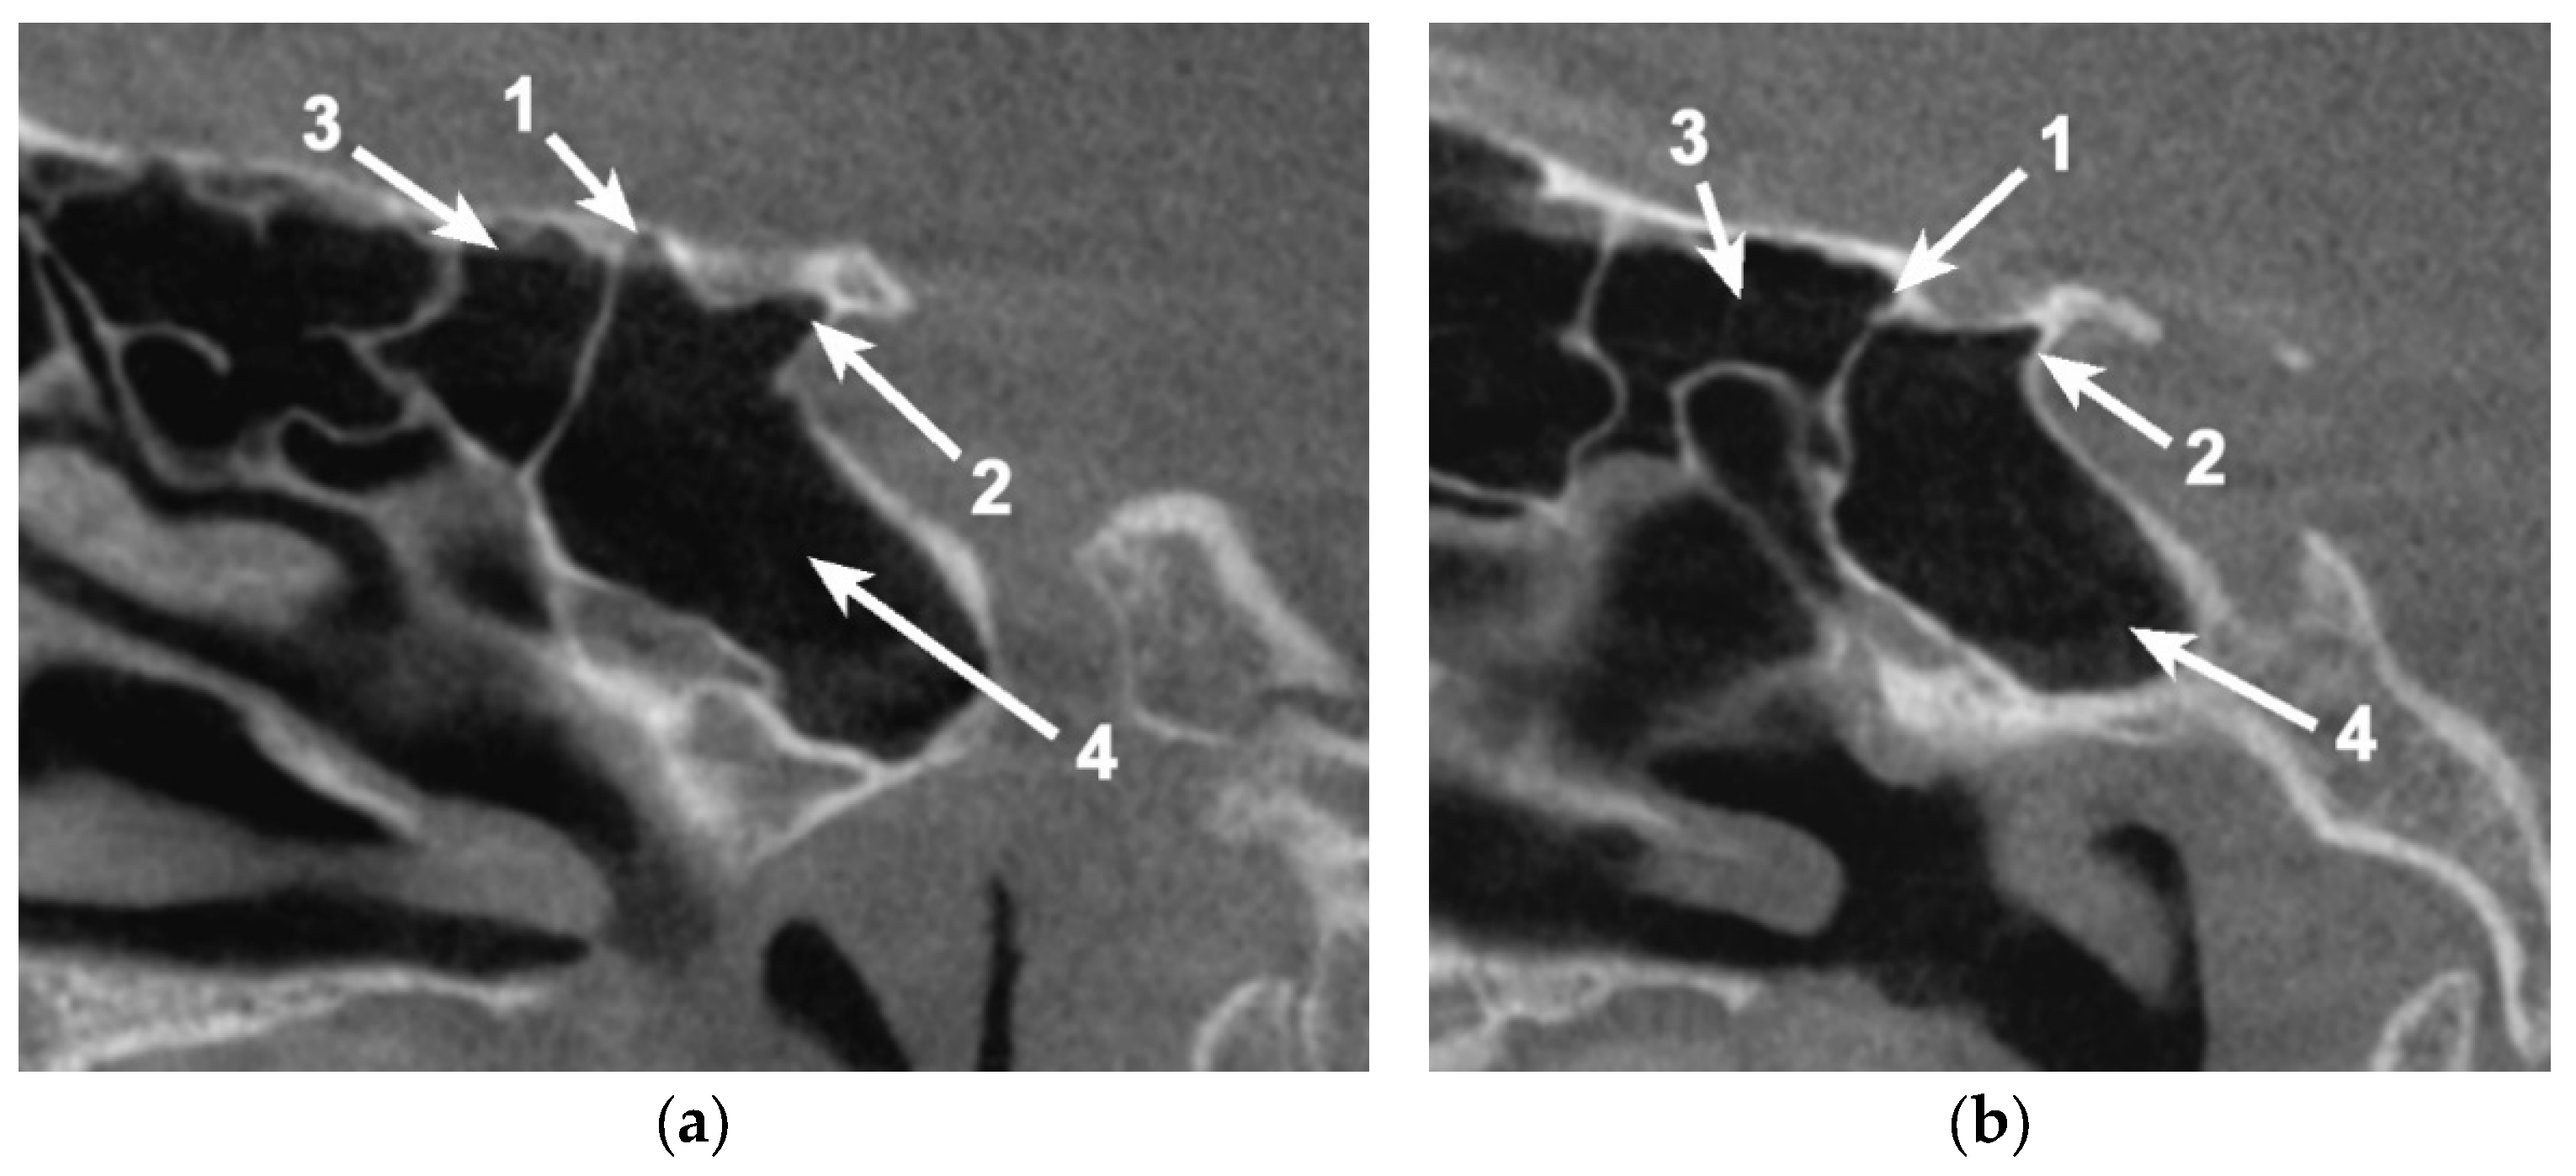

In 54/80 cases (67.5%), pneumatization within the OS could be identified (Figure 4). In eight cases (8.75%—six unilateral and two bilateral cases), the pneumatization of the sphenoid bone passed the OS, reaching the ACP.

Figure 4. Bilateral sagittal CBCT reconstruction, demonstrating the pattern of pneumatization of both the optic strut and anterior root (AR) of the lesser sphenoidal wing. (a) Left side. (b) Right side: 1. Pneumatized AR; 2. Pneumatized OS; 3. Onodi cell; 4. Sphenoid sinus.